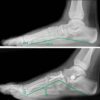

Positive Outcomes of Medial Arch-Hindfoot Reconstruction in Children

Although surgical alignment of the rear-foot might be sufficient to achieve acceptable correction of pronation-distortion deformity, concomitant correction of the medial arch might improve functional results. These authors present experience with combined hind-foot alignment and medial arch reconstruction by...